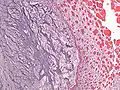

| Micrograph of an atrial myxoma. H&E stain. | |